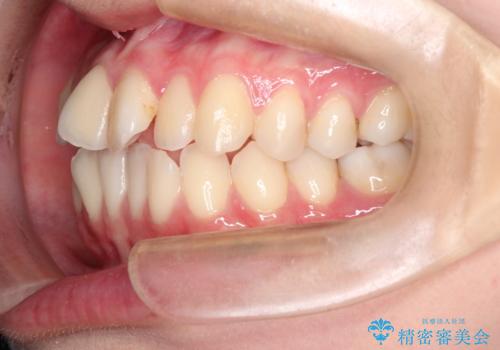

インビザラインによる非抜歯矯正 ガタガタな歯並びを整った歯並びへ

- 前歯のガタガタを主訴に来院されました。

抜歯矯正も考えられる状態でしたが、非抜歯矯正を希望されました。

使用時間を守っていただけたので、スムーズに治療を終わることができました。